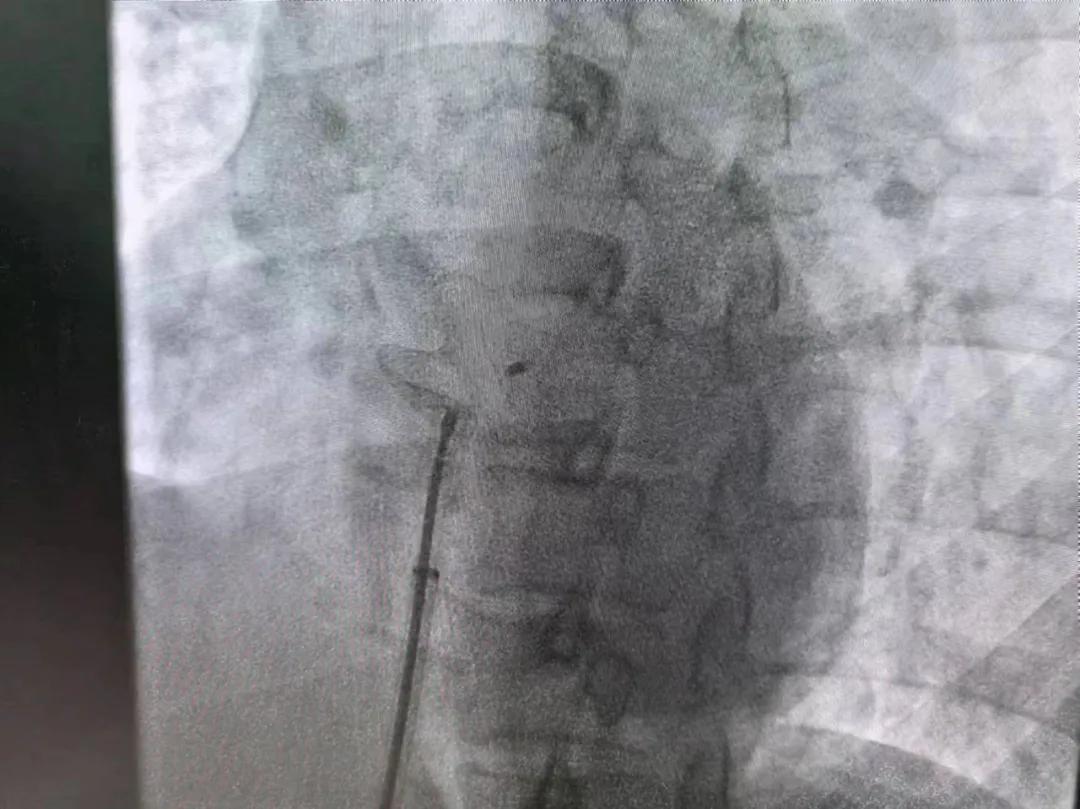

市二院:先天性心臟病介入診療 再創(chuàng)佳績(jī)

繼3月14日市二院成功開展首例卵圓孔未閉介入封堵術(shù)之后,3月21日上午,市二院院長(zhǎng)王瑾及心血管內(nèi)科主任李慧新帶領(lǐng)心血管內(nèi)科介入團(tuán)隊(duì),再次成功為患者實(shí)施“經(jīng)皮房間隔缺損封堵術(shù)”,手術(shù)過(guò)程順利。該例病人的成功手術(shù)及康復(fù),標(biāo)志著市二院心血管內(nèi)科在結(jié)構(gòu)性心臟病介入診療中再次達(dá)到了新高度。

患者為中年女性,41歲,近2年一直反復(fù)出現(xiàn)頭暈、頭痛,曾先后在多家醫(yī)院就診。近期患者癥狀加重,出現(xiàn)活動(dòng)后氣喘合并胸悶癥狀,來(lái)到心血管內(nèi)科就診。經(jīng)心臟彩超檢查顯示:患者房間隔下段連續(xù)性中斷,缺損直徑達(dá)到了13mm,肺動(dòng)脈壓已經(jīng)輕度增高,確診為房間隔缺損。

對(duì)于房間隔缺損面積較大的患者,如果長(zhǎng)時(shí)間不注意,不及時(shí)介入封堵治療,心功能可能會(huì)出現(xiàn)嚴(yán)重問(wèn)題,一旦出現(xiàn)嚴(yán)重肺動(dòng)脈壓高壓及心力衰竭,將喪失診療機(jī)會(huì),會(huì)嚴(yán)重降低患者生活質(zhì)量,且極大縮短患者壽命。

于是,院長(zhǎng)王瑾會(huì)診后,詳細(xì)詢問(wèn)患者病史,認(rèn)真分析臨床癥候群并準(zhǔn)確診斷,耐心做好患者及家屬病情告知和充分溝通。經(jīng)過(guò)完善的術(shù)前評(píng)估及準(zhǔn)備,心血管內(nèi)科介入團(tuán)隊(duì)成功為患者實(shí)施“經(jīng)皮房間隔缺損封堵術(shù)”,手術(shù)過(guò)程順利。近日,患者已順利康復(fù)出院。 (尹紅婭 潘長(zhǎng)林)